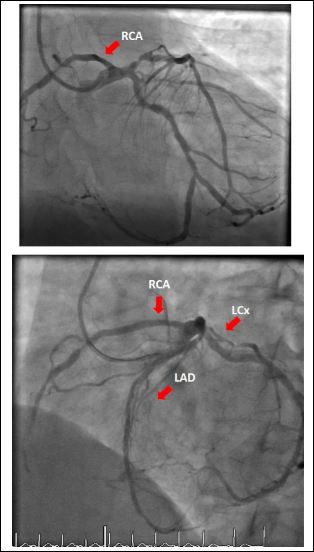

Case 5

The fifth case was a 57-year-old male who presented with an anterior STEMI. During primary PCI, it was noted that the RCA originated from left main coronary artery (Figure 11). The mid to distal RCA was sub totally occluded. Primary PCI of the culprit proximal-LAD lesion was done successfully. His echocardiography did not reveal any associated other congenital heart diseases. The residual disease in the anomalous distal RCA was left for medical therapy.

Figure 11: Right Coronary Artery (RCA) originates from the Left Main coronary artery (LM).